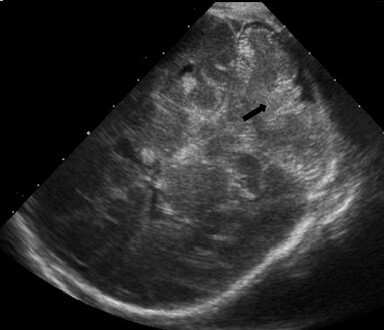

Neonatology Cerebellar Vallecula 1 Image